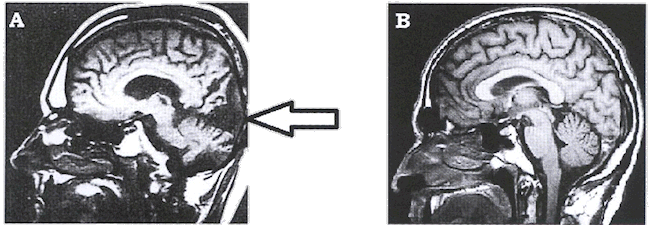

Document A : IRMf d'un patient aveugle suite à un accident

vasculaire

Document B : IRMf d'un sujet sain

Le tissu cérébral sain apparaît en niveaux de

gris plus ou moins clair. Une zone habituellement claire, devenue

noire, peut être interprétée comme une zone

lésée inactive.

Le document 1 précise que les yeux fonctionnent

Le document 2 localise (flèche) une unique zone

sombre lésée

Les yeux fonctionnent, le message est bien transmis jusqu'au

cerveau par les voies visuelles mais le cortex visuel ne

perçoit pas l'information d'où la

cécité (le patient voit sans en être

conscient : vision aveugle)